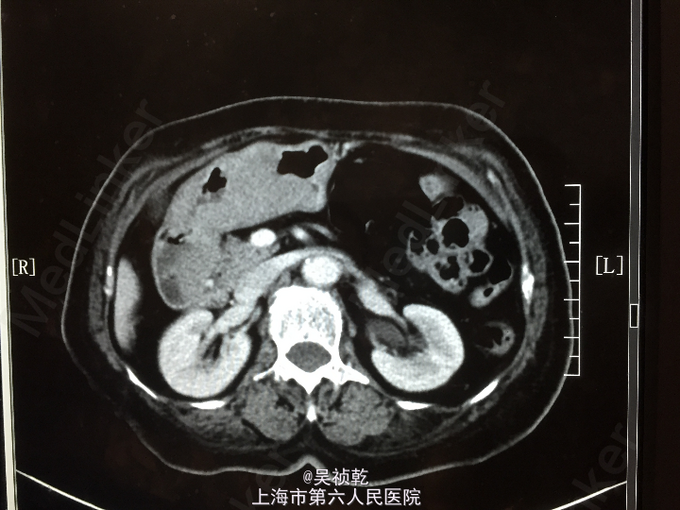

查体:T 36.8℃ P 85 次/分 R 24 次/分 BP 130/96 mmHg。神志清醒,呼吸平稳,皮肤粘膜无黄染,无贫血貌。全身浅表淋巴结未触及肿大。呼吸音清,未闻及干湿性啰音,部位双肺。心脏:心率80次/分,律齐,无杂音。腹部视诊:腹部平坦,右下腹可见手术疤痕,无腹壁挫裂伤或擦伤;触诊:腹壁柔软,全腹无压痛,无反跳痛;未触及肝,未触及脾。叩诊:无肝脏浊音界缩小或消失,无移动性浊音,肝区无叩痛,肾区无叩痛。听诊:肠鸣音正常。 辅查:2014-6-11 生化检验报告:总蛋白 64 g/L ,白蛋白 36 g/L ,白/球比例 1.3 ,谷丙转氨酶 7 U/L ,谷草转氨酶 15 U/L ,线粒体谷草转氨酶 7 U/L ,总胆红素 5.0 μmol/L ,直接胆红素 2.5 μmol/L ,总胆汁酸 4.4 μmol/L ,前白蛋白 147 mg/L ↓,尿素 4.7 mmol/L ,肌酐 60 μmol/L 。门诊化验检验报告:白细胞 4.0 *10^9/L ,红细胞 3.17 X10^12/L ↓,血红蛋白 82 g/L ↓,细胞比积 25.9 % ↓,血小板 371 X10^9/L ↑,中性细胞百分比 61.1 % 。门诊化验检验报告:凝血酶原时间 12.2 秒 ,国际标准化比率 1.11 ,部分凝血活酶时间 24.0 秒 ,纤维蛋白原 2.994 g/L ,凝血酶时间 21.6 秒 ↑。生化检验报告:血糖 4.54 mmol/L 。放免DPC(同位素)检验报告:甲胎蛋白(AFP) 4.60 ng/mL ,癌胚抗原(CEA) 2.01 ng/mL ,糖类抗原(CA125) 11.14 U/mL ,糖类抗原(CA199) 11.77 U/mL 。免疫检验报告:抗丙肝病毒抗体 阴性 。放免DPC(同位素)检验报告:游离T3 4.04 pmol/L ,游离T4 15.94 pmol/L ,促甲状腺激素 0.23 mIU/l ↓。2014-6-10 CT报告检查报告:1.胃窦部胃壁不规则增厚伴强化,符合胃癌表现,请结合临床。2.肝左内叶低密度灶,转移瘤可能,建议MRI增强进一步检查。3.肝内散在囊肿。CT报告检查报告:下腹部增强CT未见明显异常。2014-6-12 病房心超检查报告:左室、右室右房大小在正常范围。

入院后完善术前检查,胃镜及CT提示胃部肿瘤,胃癌可能,经积极术前准备,于2014.06. 16全麻下行胃癌根治术:患者麻醉达成后,平卧位,胃肠减压,留置导尿,常规消毒铺巾。切口:上腹部正中切口,上起剑突,下绕脐左侧达脐下3cm,切除剑突。进腹后探查:肝脏、腹膜、盆腔、肠系膜上血管根部及腹主动脉周围淋巴结(-)。远侧胃见胃窦大弯侧隆起型肿块,直径4*6cm,界不清,未累及浆膜,向远侧累及十二指肠。行胃癌根治术,D2。术野仔细止血,用43℃蒸馏水冲洗腹腔,给予法马新40mg+生理盐水100ml浸泡手术区域。吸尽后,于十二指肠残端及胃床放置引流,清点纱布、器械无误后,逐层关腹;术程顺利,术中出血约300ml,标本及淋巴结送病理,病人安返。术后病理检查报告:胃 ▉标本类型:根治性胃大部切除标本▉肿瘤部位:肿瘤位于胃窦及胃体,距上切 2.5CM,距下切 0.8CM▉大体类型:浸润型,大小: 11× 7 CM▉组织学类型:弥漫性大B细胞恶性淋巴瘤 ▉肿瘤浸润深度:全层 ▉血管浸润:(-),淋巴管浸润(+),神经周围浸润(+)▉切缘:上下切缘均未见肿瘤浸润▉区域淋巴结: 以下均见肿瘤浸润: 胃小弯LN5/8枚、胃大弯侧LN2/10枚。 以下均未见肿瘤浸润: (肝动脉旁)LN0/1枚。▉肿瘤旁病变:慢性胃炎 ▉淋巴结免疫反应状态:SH(+),PH(+),GH(+)▉肿瘤间质反应:淋巴细胞﹑浆细胞﹑组织细胞反应(+),纤维组织增生反应(+)胃窦及胃体:弥漫性大B细胞恶性淋巴瘤,肿瘤侵及胃壁全层。肿瘤组织免疫酶标记结果:CD20(+)、CD79a(+)、CD3(-)、CD5(-)、Bcl-2(+)、Bcl-6(+)、CD10(+)、Mum-1(-)、PAX-5(+)、CD30(-)、CD15(-)、Ki-67(80%+)、Her2(-)、CK(-)、LCK(-)、CK19(-)。 术后诊断更正为:胃弥漫性大B细胞恶性淋巴瘤。术后予以抗感染止血支持治疗,患者恢复尚可,术后予以进食后,患者反复呕吐,查胃镜及消化道造影,考虑胃动力不足,予以胃肠减压,促胃动力治疗,加强肠外营养,纠正水电解质失衡。术后患者出现肺炎予以抗感染治疗,肺部感染好转。7.16患者出现消化道出血、血象三系降低,血压降低、经止血、输血、升血小板对症治疗后仍未见明显好转;7.17并发呼吸功能不全,血压下降,予以呼吸支持,通畅气道,多巴胺升血压,考虑须行气管插管等有创抢救措施,家属签字放弃此类抢救措施。因血色素偏低,于7.16和7.17分别输红细胞2u、血浆200ml,无特别输血反应。2014-07-19凌晨1点患者出现血压下降,心脏停博,经抢救无效后死亡。